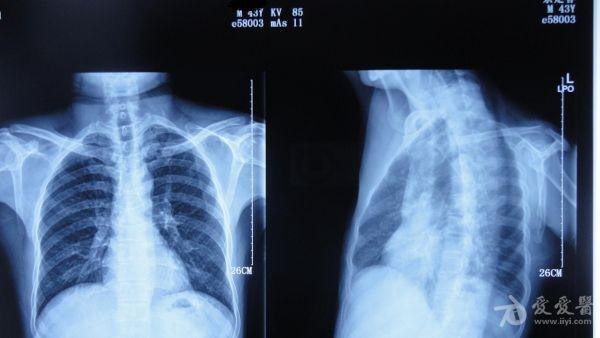

患者**,男,43岁,2个月前因不慎摔伤致左锁骨内侧骨折,行保守治疗,锁骨、前臂吊带固定。定期拍片复查,最近一次X片示骨折断端内侧向后上移位,外侧向前下移位。于12月20日诊断以“左锁骨骨折骨不连2月余”入院。专科检查:左锁骨压痛叩击痛,外形畸形,肩关节活动受限。昨日在臂丛下行骨折切开复位内固定术,用三枚克氏针固定。大家看一下,讨论讨论有什么更好的办法吗?受伤时

入院时拍的